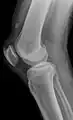

![]() | |

| An x-ray demonstrating quadriceps tendon rupture. Note the abnormal angle of the patella and soft-tissue swelling marked by the arrow. | |